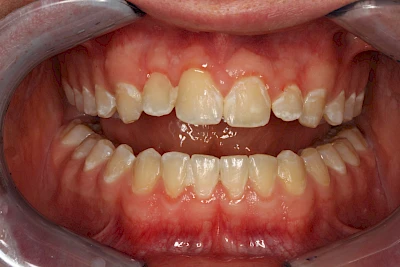

Gerade bei Kindern und Jugendlichen werden zunehmend häufiger bräunliche Verfärbungen mitunter auch mit Formveränderungen (die Oberfläche ist rauh oder zerklüftet) der Zähne beobachtet. Meist sind Schneidezähne oder Backenzähne betroffen. Dies könnte ein Hinweis auf sogenannte Kreidezähne (MIH: Molaren-Inzisiven-Hypomineralisation) sein.

Bräunliche Verfärbung